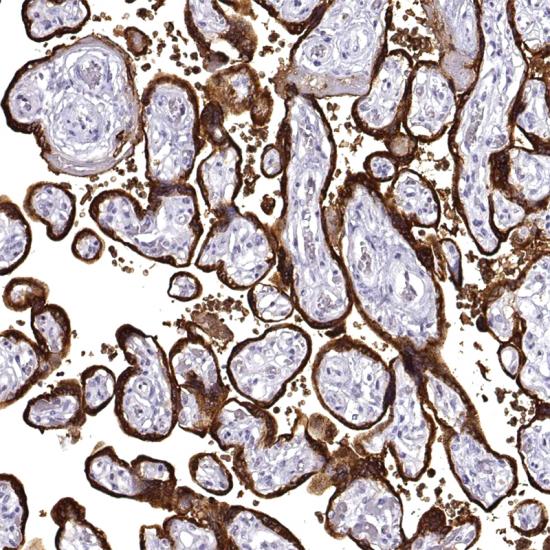

Human Placental Lactogen抗體試劑(免疫組織化學) 閩廈械備20180229號

• 陽性部位:

細胞漿

• 陽性對照:

胎盤

Human Placental Lactogen是存在于人正常胎盤的一種蛋白。在正常的胎盤、葡萄胎和滋養(yǎng)層及非滋養(yǎng)層的腫物,其染色方式與HCG相似,中間的滋養(yǎng)層細胞優(yōu)勢表達HPL,只有局部表達HCG。主要用于胎盤原位滋養(yǎng)細胞瘤及絨癌的鑒別。